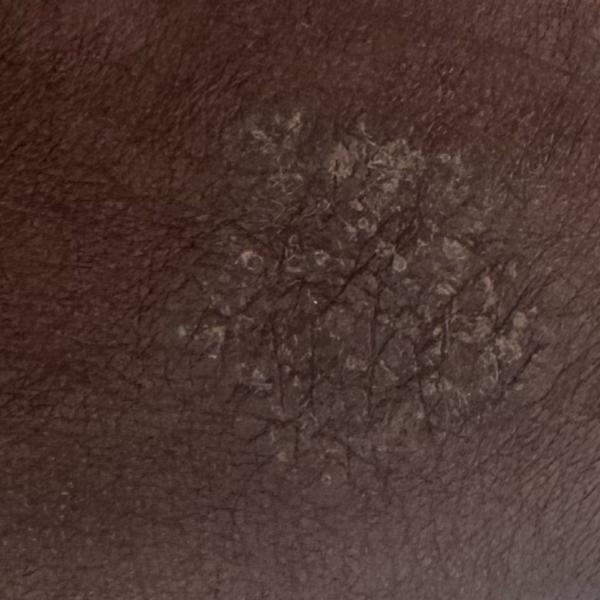

Best skin doctor in trichy

Vibha Skin Hair and Laser Clinic